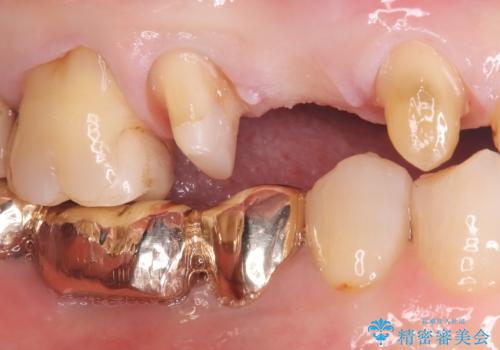

- 主訴:ブリッジの歯が一部欠けた

右上⑤4③でメタルフレームを用いたブリッジが既に入っており、その内右上5番目の歯がう蝕により欠けてしまっていました。

右上5はう蝕除去後は間接覆髄を行いCR裏層しています。う蝕が大きく神経症状が出ないか経過を確認しクラウンの印象を行っています。